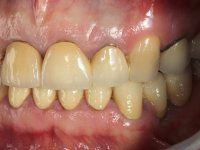

Foi proposto ao paciente fazer uma reabilitação total com infraestruturas em zircónia revestidas a cerâmica. No maxilar superior, seriam realizadas 6 coroas (1.3/1.2/1.1/2.1/2.2/2.3), uma ponte de 3 elementos (1.4/1.5/1.6) e uma ponte de 4 elementos (2.4/2.5/2.6 e 2.7). No maxilar inferior, foram propostas 7 coroas (4.3/4.2/4.1/3.1/3.2/3.5 /3.6) e duas pontes (4.4//4.5/4.6) e (3.3/3.4#/3.4).O objetivo seria subir a D.V.O., descruzar a mordida do lado direito, eliminar as infiltrações e as exposições radiculares e reabilitar o paciente com estruturas protéticas com aspeto mais natural.

A primeira acção terapêutica foi tentar melhorar o tratamento endodôntico dos dentes (2.4/2.5/4.2)). A sua manutenção em boca seria condicionada pelo sucesso desta intervenção. Seguidamente foram feitas impressões em alginato e registo inter-maxilar em silicone para confeção em laboratório de uma ponte provisória em acrílico com reforço. O objetivo desta ponte provisória seria ensaiar o aumento da D.V.O. e descruzar a mordida do lado direito. Foi utilizado um monobloco de 13 dentes com o dente 2.6 com o pôntico. As coroas e as pontes foram removidas e os remanescentes coronários foram repreparados. A ponte provisória foi rebasada primeiramente com acrílico auto-polimerizável e de seguida com resina composta. Após 2 semanas de permanência em boca, foram feitas as impressões para confeção da ponte provisória inferior também realizada em laboratório. Especial cuidado foi colocado na remoção das coroas antigas, sendo feito primeiramente um corte axial que permitiu que fossem removidas de uma forma menos traumática. A temporização foi feita durante 8 semanas, permitindo que os tecidos gengivais estabilizassem posicionalmente. As impressões definitivas foram realizadas após afastamento gengival utilizando a técnica do fio único impregnado. Foi utilizada a técnica de dupla mistura com dupla viscosidade (putty soft e light).Simultaneamente foi realizada a recolha das relações inter-maxilares e o registo com arco facial. Foram confecçionados os modelos de trabalho e feita a sua correta montagem em articulador semi-ajustável. Em seguida foram feitas infra estruturas em zircónia que posteriormente foram revestidas por cerâmica. A prova de “biscoito” foi realizada em boca para avaliação estética e funcional sendo também avaliado o seu assentamento e ajuste. A reabilitação definitiva foi cimentada em boca utilizando um cimento de ionómero de vidro reforçado por resina.